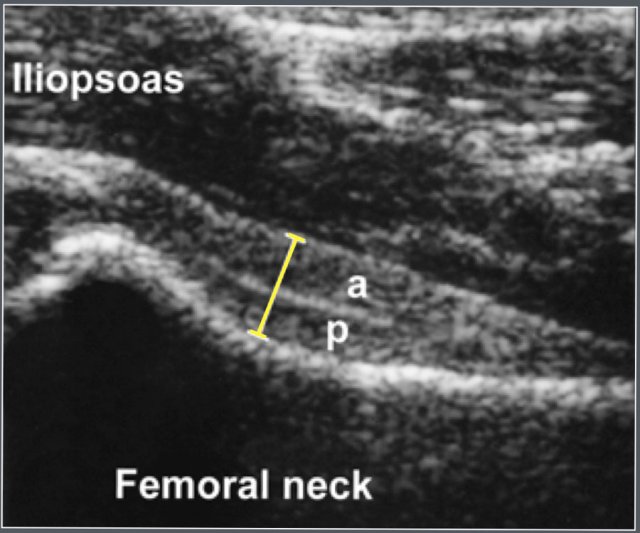

Anterior recess

Materials and method

Ultrasonographic study of 58 healthy children and 105 children with unilateral transient synovitis (age range 1.7-12.8 years).

The children were examined in the supine position with hips in neutral position.

Adapted from reference 22 Adapted from reference 22

The children are examined in the supine position with hips in neutral position.

The anterior joint capsule was measured, including both of its components (the anterior and posterior layer).

Also the anterior contour of the joint casule is evaluated.

There was no statistically significant correlation between age and thickness of the anterior joint capsule.

A difference >2mm or an effusion >2mm is considered abnormal.

Ultrasonographic measurement of the anterior joint capsule. Both anterior (a) and posterior (p) layer can be identified.